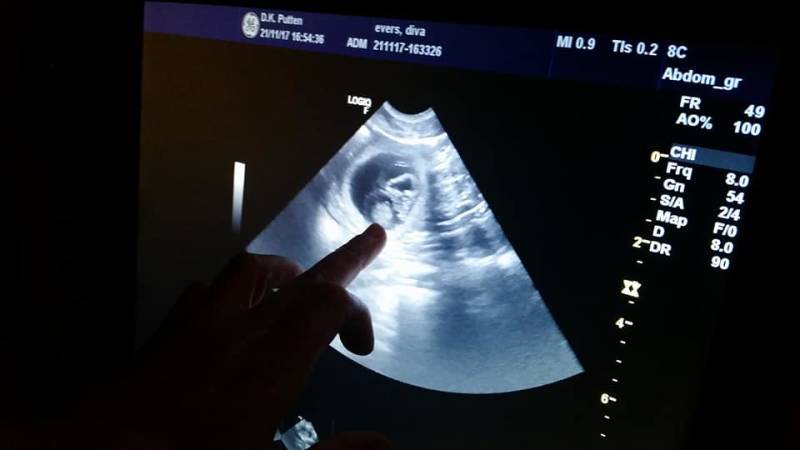

Zora is drachtig!

Het zal geen groot nest worden waarschijnlijk, maar er zijn sowieso 4 verschillende vruchtzakjes gespot op deze (eigenlijk veel te vroege) echo! We zitten nu op dag 25 dus het was vrij lastig om de embryo's goed in beeld te krijgen. Maar dát ze zwanger is, is zeker!

We kunnen ons nu dus echt gaan voorbereiden op een nieuwe puppy-periode! Ik kijk er onwijs naar uit. :D

De verwachting is dat de pups rond Pasen geboren zullen worden.